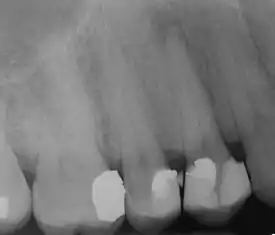

| Radiograph showing bone loss between the two roots of a tooth (black region). The spongy bone has receded due to infection under tooth, reducing the bony support for the tooth. | |